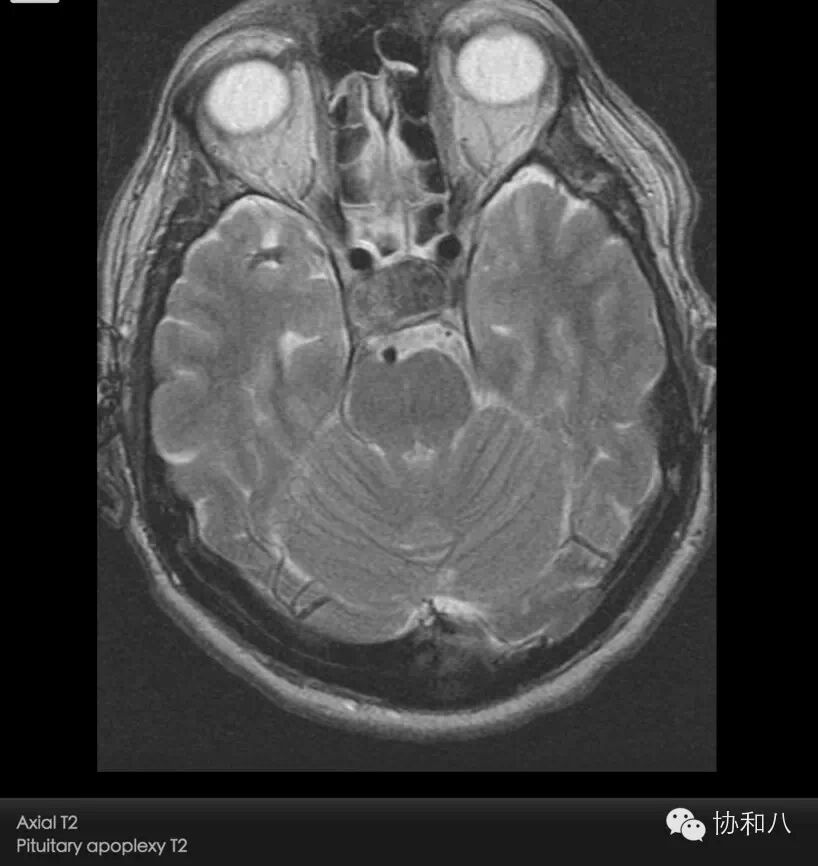

C. 轴位T2WI

垂体信号不均,呈混杂信号,可见明显低及高信号区,符合出血及坏死囊变表现。